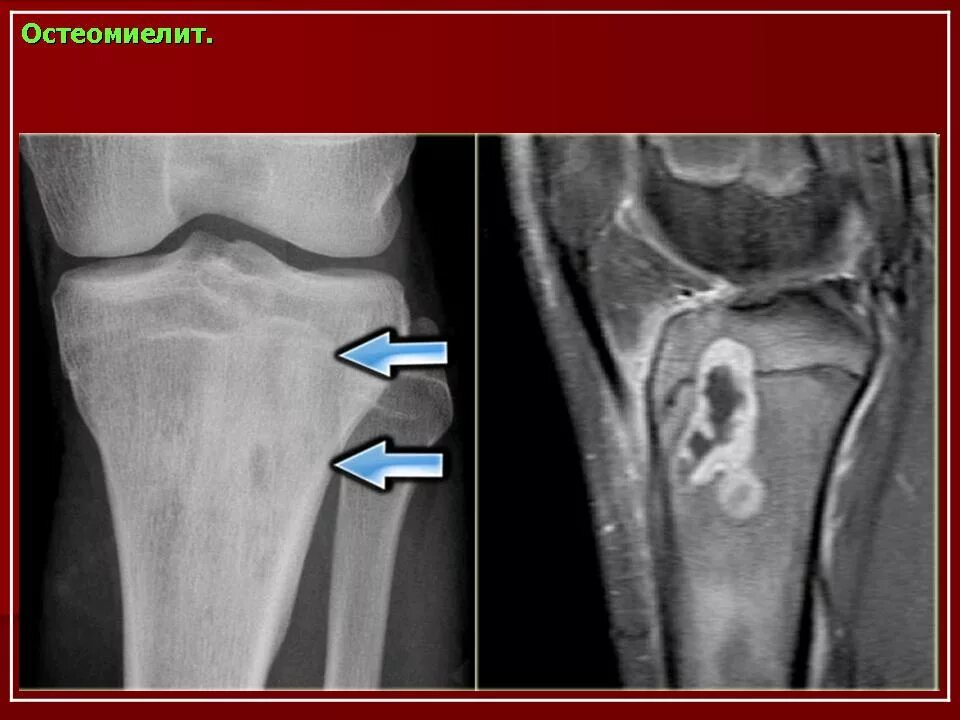

Деструктивные изменения суставов